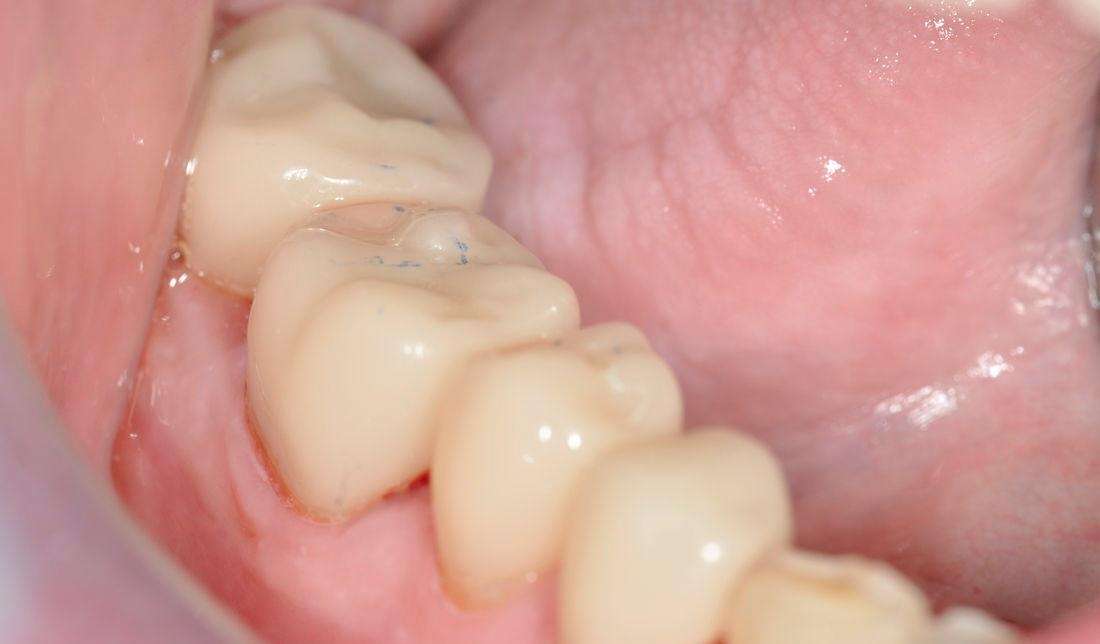

Crown

Click image to see a larger picture

After